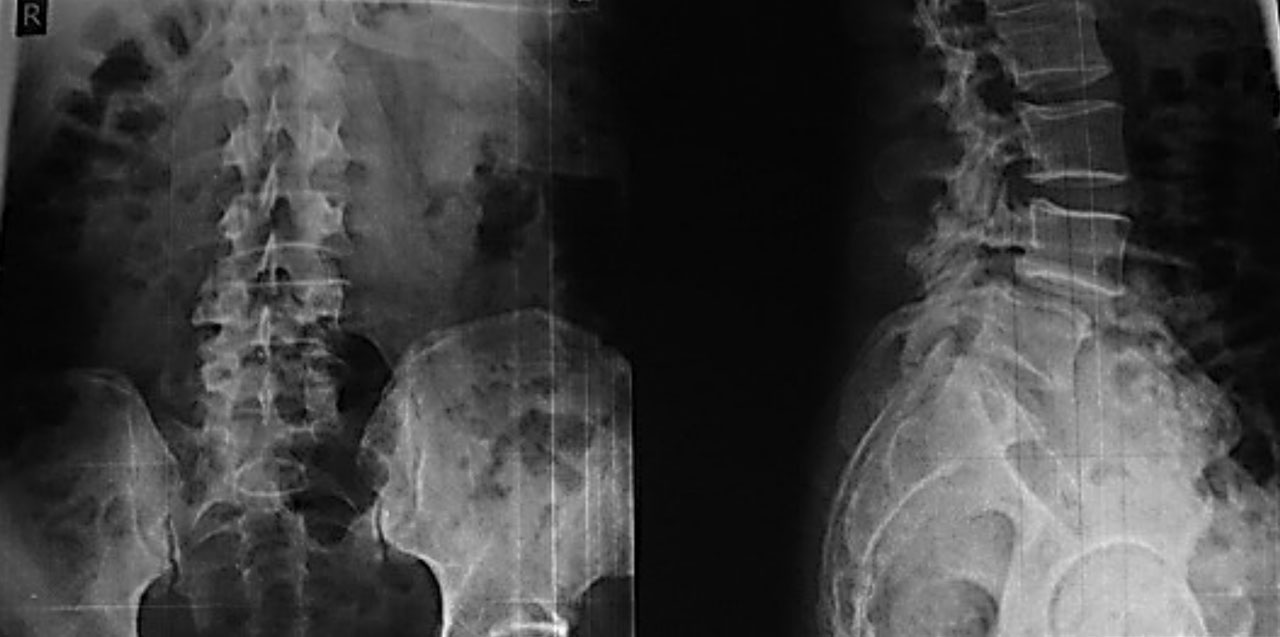

Рентген поясницы: анатомические особенности и медицинские исследования